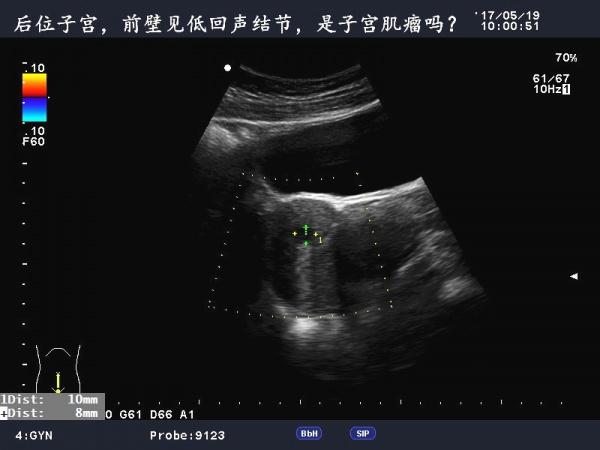

这是巧克力囊肿吗?

患者女,40Y,因下腹部疼痛就诊,最近一次月经来潮量少且疼痛厉害,以往基本上正常。

于月经第11天行B超检查。

请大家指导指导,谢谢!